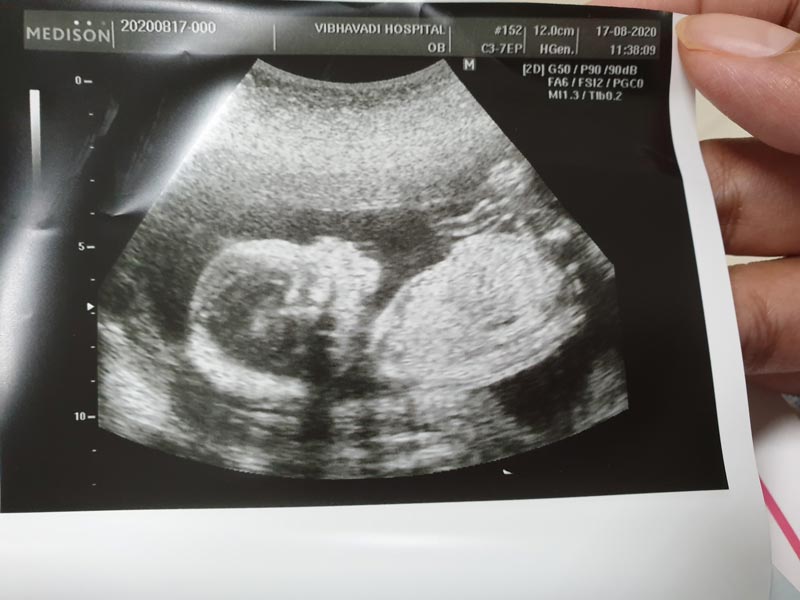

ล่าสุด (10 กันยายน 2563) นิกกี้ พิ้ม ก็เผยข่าวดีว่า เดน่า ภรรยาสาว ได้ตั้งท้องลูกคนแรกเป็นที่เรียบร้อยแล้ว และขณะนี้ก็มีอายุครรภ์ได้ 5 เดือนแล้วด้วย ซึ่งเจ้าตัวก็ออกมาเผยภาพขณะโอบกอดภรรยาคนสวยจากข้างหลัง พร้อมเผยให้เห็นภาพภรรยาที่กำลังอุ้มท้องลูกน้อยอยู่ เป็นภาพที่อบอุ่นหัวใจมาก ๆ